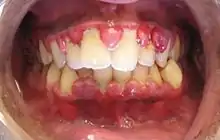

Gingival enlargement can be a feature in some periodontal diseases.

Photograph (left) and a radiograph (right) demonstrating extensive bone loss and soft tissue inflammation due to periodontitis. Plaque, calculus and staining